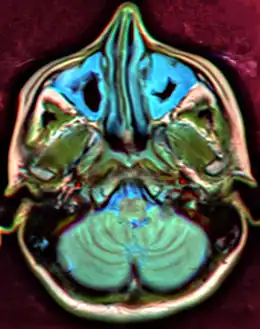

MRI image showing sinusitis. Edema and mucosal thickening appears in both maxillary sinuses.